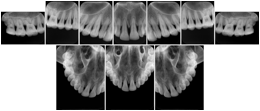

2. A patient requests cosmetic surgery to enhance their facial appearance. The case requires consultation between an orthodontist in New York and an oral surgeon in California. The cephalometric series of 2D projections constructed from a volumetric CT data set that is used for the discussion is arranged by a Structured Display for transfer between the two practitioners.

Cephalometric Series Structured Display

Figure OO-2. Cephalometric Series Structured Display